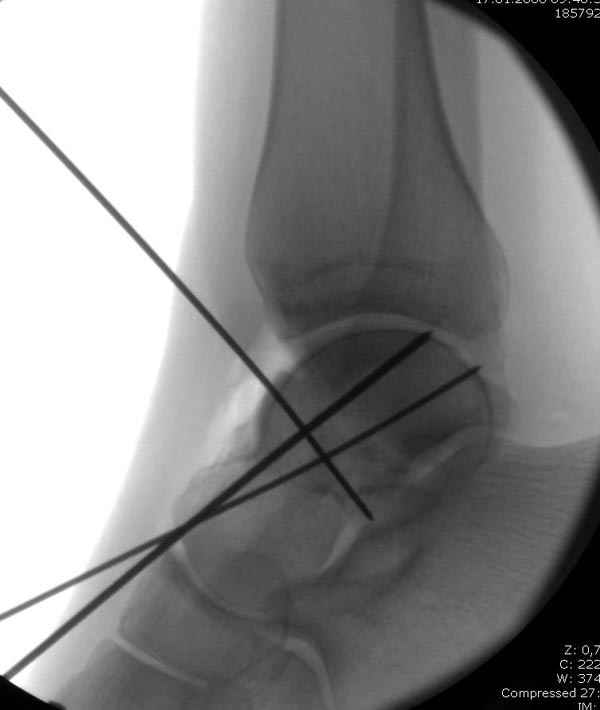

Вдогонку по поводу перелома таранной кости, больная 81, не страдает диабетом, перелом закрытый, в первый же день поступления ограничились временным наружным фиксатором (как на снимке).

Из-за отека на стопе тактика лечения у всех была

одинаковая: временная наружная фиксация до спадения отека, при изолированных переломах они выписывались домой и через дней 7 госпитализировались на оперативное лечение.

Примеры на снимке...